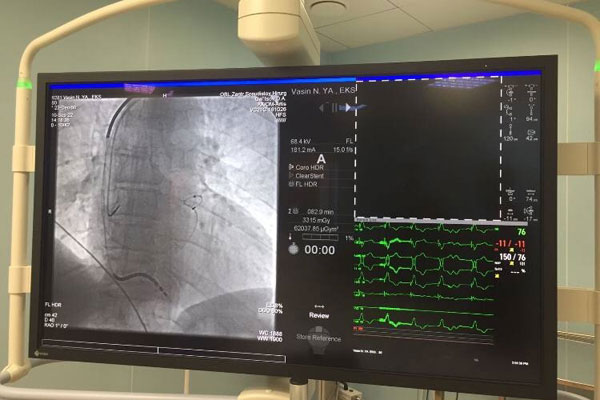

ИЗУЧАЕМ ОПЫТ ОКАЗАНИЯ ВЫСОКОТЕХНОЛОГИЧНОЙ ПОМОЩИ